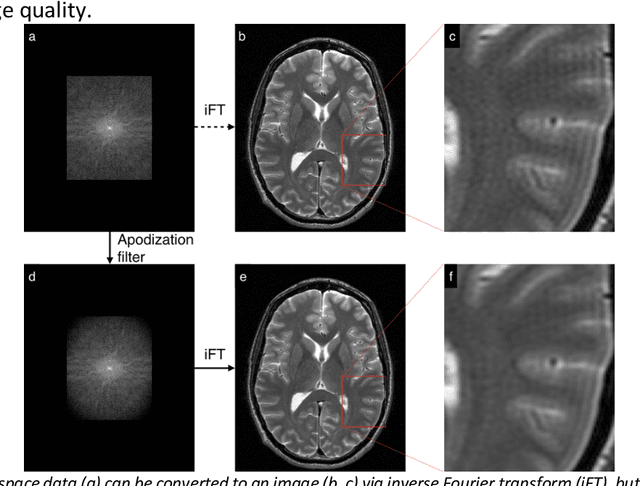

A novel deep learning-based magnetic resonance imaging reconstruction pipeline was designed to address fundamental image quality limitations of conventional reconstruction to provide high-resolution, low-noise MR images. This pipeline's unique aims were to convert truncation artifact into improved image sharpness while jointly denoising images to improve image quality. This new approach, now commercially available at AIR Recon DL (GE Healthcare, Waukesha, WI), includes a deep convolutional neural network (CNN) to aid in the reconstruction of raw data, ultimately producing clean, sharp images. Here we describe key features of this pipeline and its CNN, characterize its performance in digital reference objects, phantoms, and in-vivo, and present sample images and protocol optimization strategies that leverage image quality improvement for reduced scan time. This new deep learning-based reconstruction pipeline represents a powerful new tool to increase the diagnostic and operational performance of an MRI scanner.